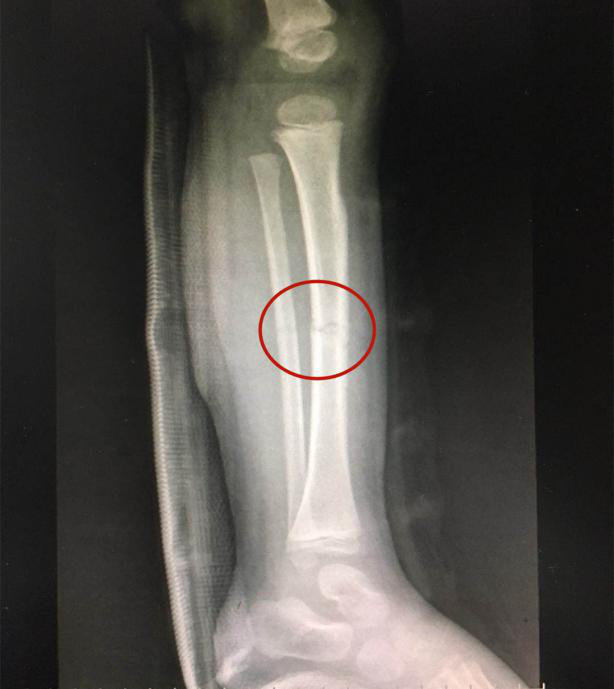

接診的瀘州市中醫(yī)醫(yī)院骨傷一科副主任中醫(yī)師李孟澤查看了患兒之前的X光片及左下肢情況,發(fā)現(xiàn)其骨折移位較大(骨折處彎曲呈30度角以上),導(dǎo)致左下肢中段嚴(yán)重畸形。

手法復(fù)位前X片顯示脛腓骨斷端,左下肢中段嚴(yán)重畸形